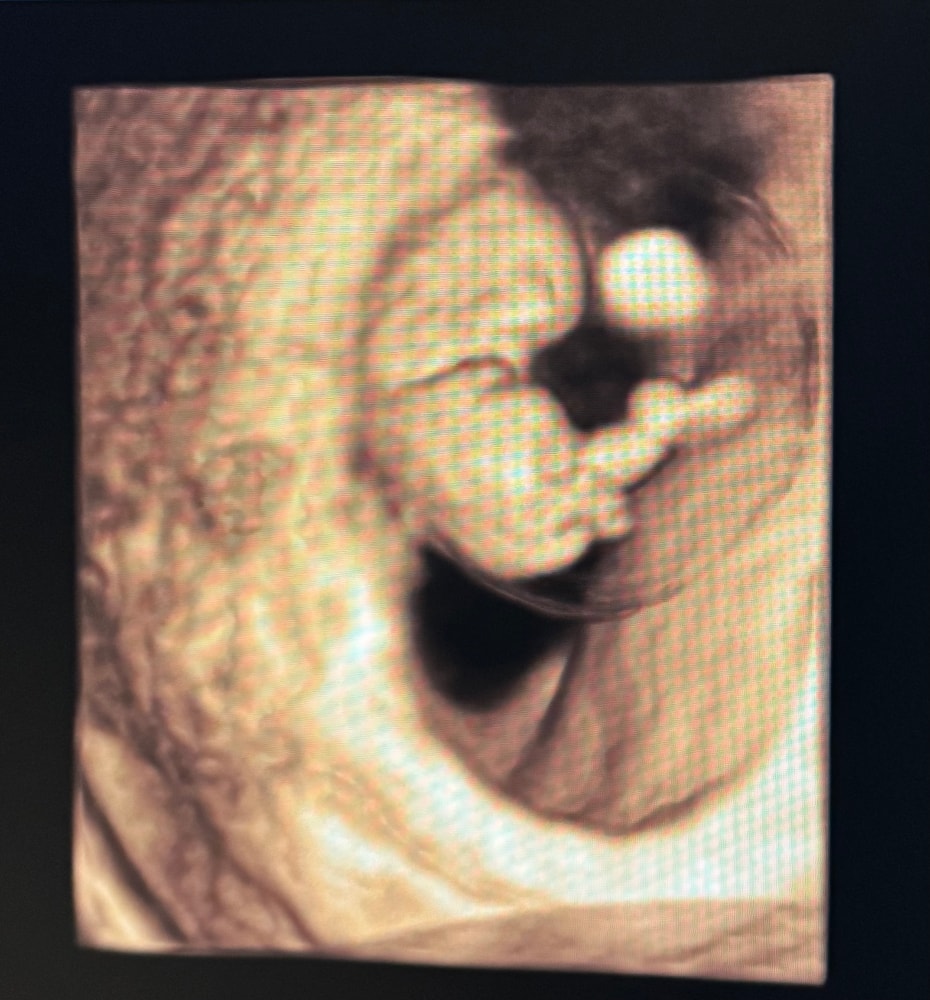

сразу побежала на УЗИ. Мальчишка на месте, ручки-ножки есть. Чсс 173. По узи нет ничего опасного, ни отслоек, ни гематом. Врач узи предположила, что опорожнилась гематома и еще не вышла.

Какой малышок 👶💞

Пусть все будет хорошо! Такой классный малыш в пузырьке ) Где у нас такие красивые узи делают?